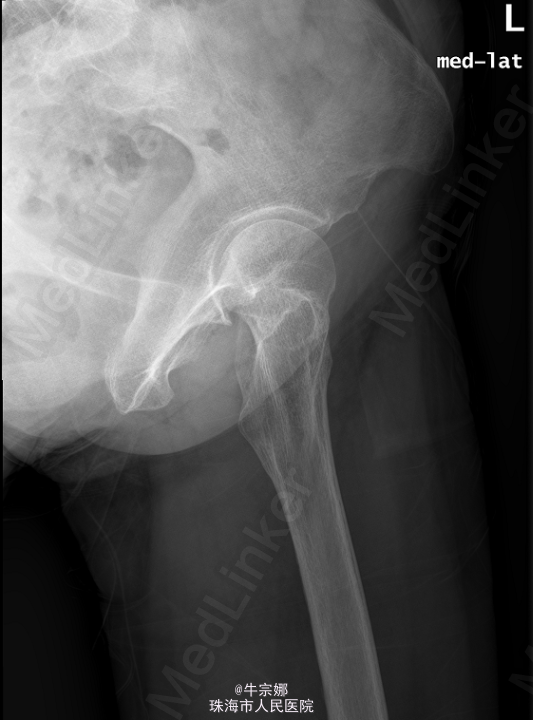

患者,女,65岁,因“外伤致左髋部疼痛伴活动受限10小时”入院。10小时前患者劳动时时不慎向后摔倒,左髋部、左肘部着地,当即感左髋部疼痛,活动受限.

左髋部皮肤完整无淤青,周围软组织无明显肿胀,局部压痛存在,左髋关节活动受限,腹股沟及鞍区感觉无明显减退,轴向叩击痛(+),左下肢无外旋畸形及短缩畸形. 2015-05-22本院CR :左股骨颈骨折. CT:左股骨颈骨折。